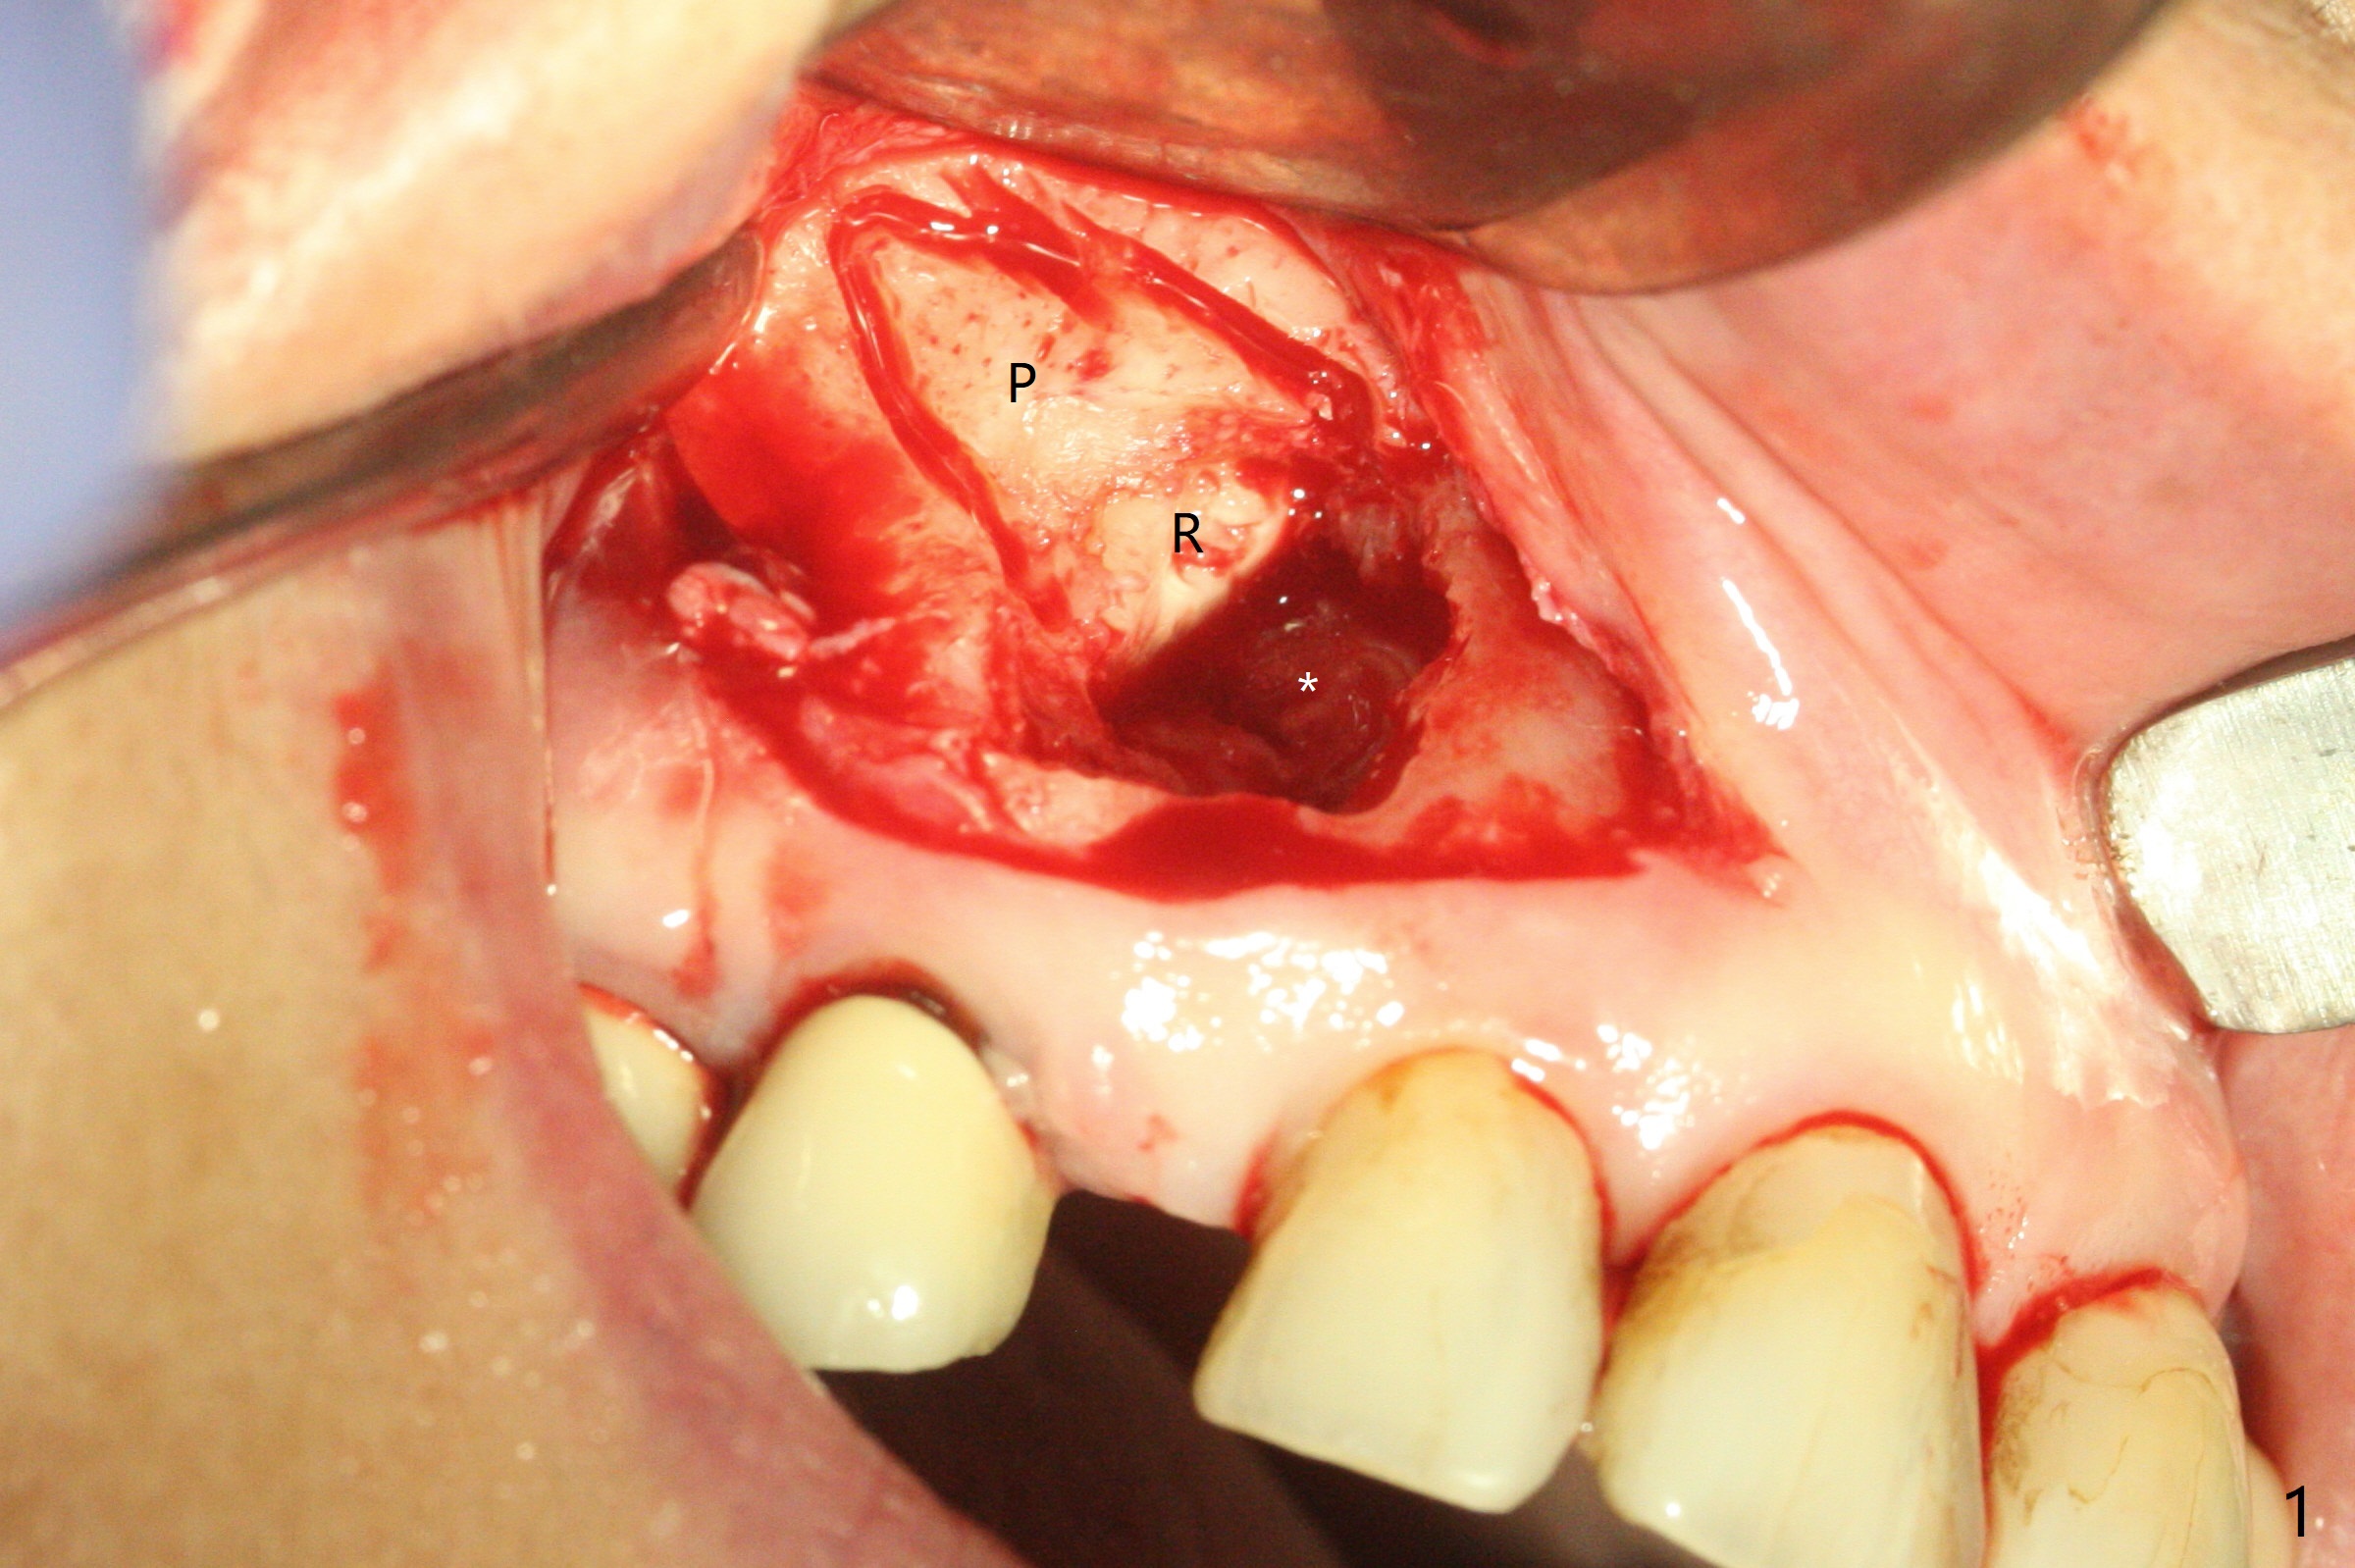

After incision and flap elevation, the crown of the impacted canine is more superficial. With removal of the buccal cortical plate and multiple sectioning of the crown, the latter is removed (Fig.1 *). Further removal of the buccal plate (P) and purchase points, the root (R) is extracted easier. In fact the apex of the root is the deepest (Fig.2). With the guide (Fig.3 G) and 2.2 mm drills, the osteotomy is established. It is pretty shallow. A 3x18 mm drill is used to deepen the osteotomy free hand (mistake: too palatal). When a 3.8x18 mm UF implant is being placed, it cannot be placed deep with the guide. When the latter is removed, the implant seems to be placed too deep and too buccal with <10 Ncm (Fig.4). A 4.5x7(5) mm abutment is placed mainly to correct the trajectory of the implant to certain degree. Placement of the implant at #3 is quite smooth (Fig.5) in spite of severe bone loss and abundant granulation tissue at #3 and 5. The implant at #5 does achieve 2 pointed fixation (Fig.4,6 arrowheads). The most coronal portion of the canine crown is left behind (Fig.6 C).